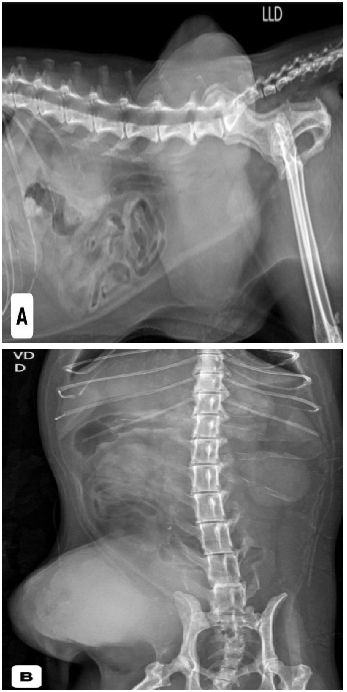

Inicialmente foram realizados dois exames citológicos, os quais apresentaram células inflamatórias e resultados inconclusivos. Foram solicitados exames de triagem oncológica e avaliação pré-anestésica, incluindo hemograma, bioquímicos hepáticos e renais, radiografias torácicas e abdominais, ecocardiograma, eletrocardiograma e ultrassonografia abdominal. Todos os exames apresentavam-se dentro da normalidade para a espécie, entretanto, a radiografia torácica evidenciou duas estruturas arredondadas, radiopacas, sugestivas de metástases pulmonares (Figura 1). A radiografia abdominal mostrou massa de densidade aumentada no abdome caudal esquerdo (Figura 2).

Figura 2: radiografia abdominal mostrou acentuada estrutura de maior radiopacidade em região lateral direita do abdômen caudal pela projeção laterolateral (A) e pela projeção ventrodorsal (B).

Fonte: Setor de imagem do Hospital Veterinário Público Anclivepa-SP, 2025.